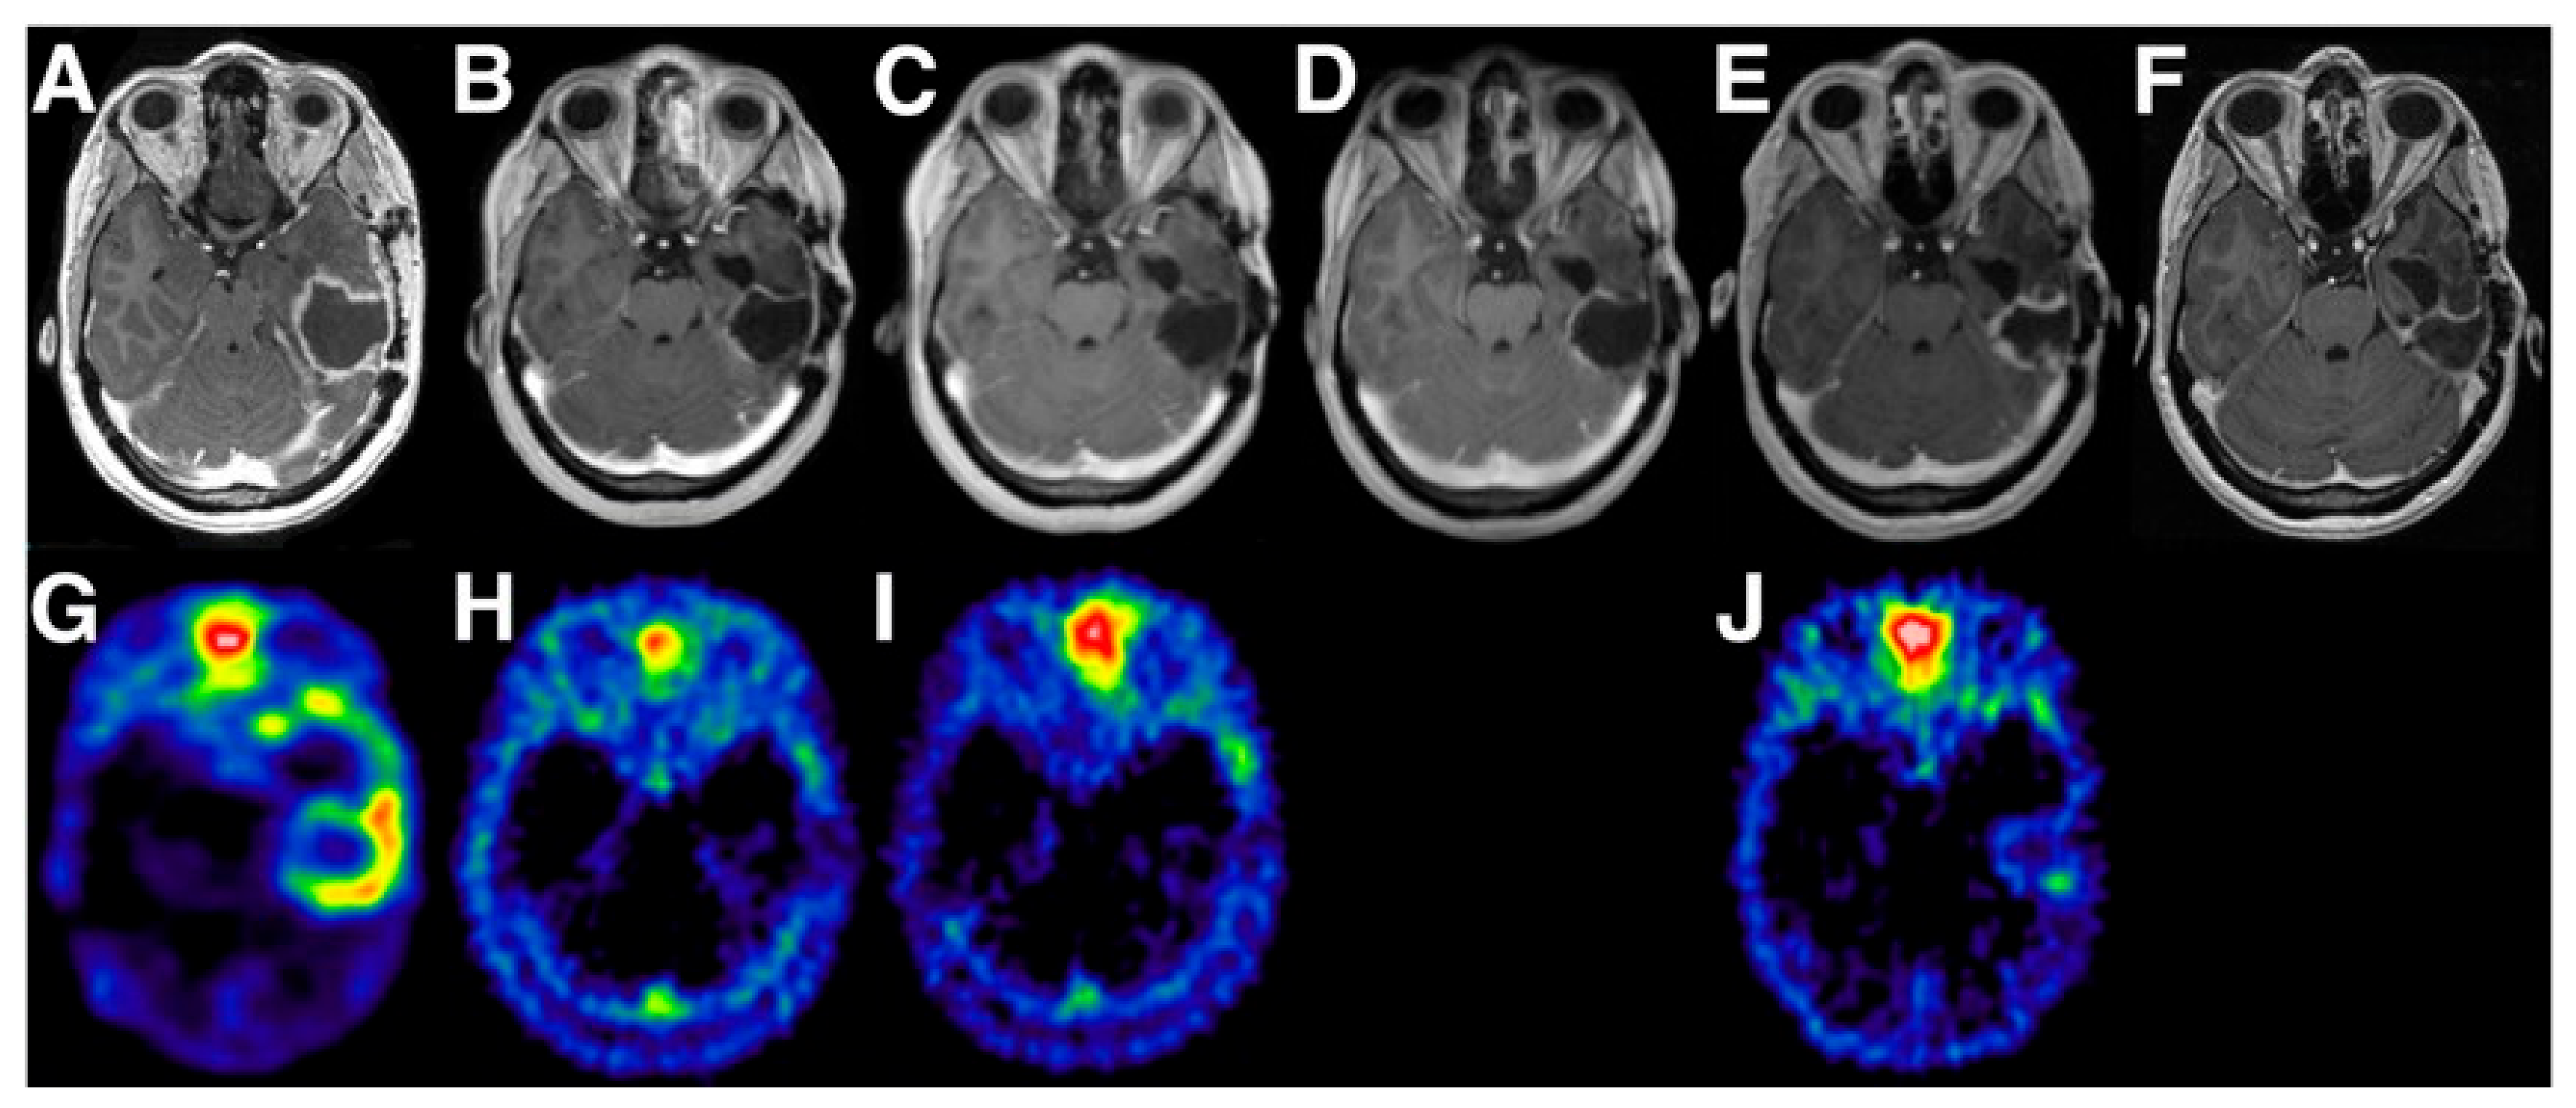

Among all diagnostic PET tracers, the most widely studied and used is [18F]-2-fluoro-2-deoxy-D-glucose ([18F]FDG). As an analog of glucose, [18F]FDG is taken up into cells by physiological glucose transport, after which it is phosphorylated to [18F]FDG-6-phosphate. Being slightly different from glucose, the phosphorylated product (FDG-6-P) is not metabolized further and remains trapped in the cell [21]. Increased cellular metabolism (i.e., glucose uptake and phosphorylation) is the underlying mechanism of higher SUVs of [18F]FDG in cancer cells compared to healthy tissue (i.e., Warburg effect) [21,22]. However, in particular in neuro-oncology studies, optimization of the TBR (i.e., contrast) is challenging because of the high physiological uptake of [18F]FDG in normal active brain tissue. To reduce uptake in healthy brain, complete fasting for a minimum of 6 h before the scan is recommended, and patients should be kept blindfolded in a quiet room during the uptake phase, or scanning times should be delayed [23]. With applying these procedures, [18F]FDG has shown acceptable sensitivity for the identification of anaplastic abnormalities in patients with low-grade glioma (LGG), high-grade glioma (HGG; Figure 1a [24]), CNS lymphoma, brain metastases, and meningioma [25,26,27]. Moreover, higher [18F]FDG uptake has shown a positive correlation with higher histologic grade and worse prognosis [26,28], making [18F]FDG PET a suitable tool for the prediction of progression-free survival (PFS) and overall survival (OS) [29]. [18F]FDG PET has shown not to be suited for radiation treatment planning, since the region of increased uptake generally covers a smaller volume than what was defined as malignant on T1-weighted gadolinium and T2-weighted MR-images [30]. In addition, [18F]FDG cannot distinguish between radiation-induced necrosis, changes in the tissue due to surgery, inflammation, or (remnant/recurrent) disease, making [18F]FDG not valuable for follow-up studies of CNS tumor therapies [21,22].

Figure 1.

Contrast-enhanced Magnetic Resonance Imaging (MRI) (top row) and multiple PET tracers for diagnostic imaging (bottom row) in glioblastoma. (a) [18F]-2-fluoro-2-deoxy-D-glucose ([18F]FDG), (b) O-(2-[18F]-fluoroethyl)-L-tyrosine ([18F]FET), (c) [18F]Fluorocholine, (d) 1-(2-Nitro-imidazolyl)-3-[18F]fluoro-2-propanol ([18F]FMISO), (e) 3′-deoxy-3′-[18F]fluorothymidine ([18F]FLT). Adapted from [24]. This research was originally published in Glioblastoma [internet]. Bolcaen, J.; Acou, M.; Descamps, B.; Kersemans, K.; Deblaere, K.; Vanhove, C.; Goethals, I. PET for therapy response assessment in glioblastoma. In Glioblastoma [Internet]; De Vleeschouwer, S., Ed.; Codon Publications: Brisbane, AU, 2017.